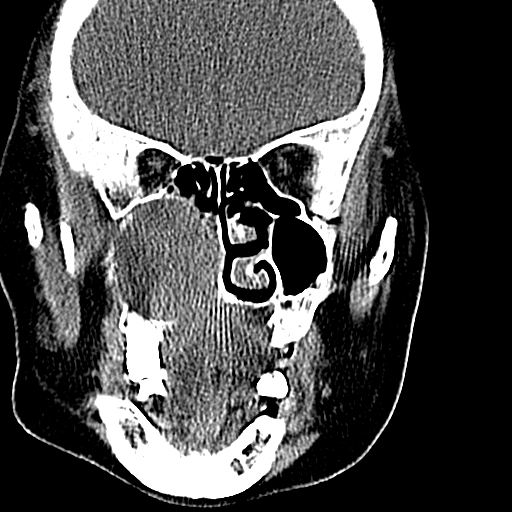

老年患者,女。鼻塞多年。

考虑右侧上颌窦良性占位性病变,粘液囊肿可能性大;建议活检。

膨胀性生长,且骨质无破坏,说明时间久,良性;从密度,边缘看,内部还见坏死区,应该是实性肿瘤,定性,影像学无绝对的特异性

病灶密度很不均匀,骨壁膨胀中有断裂,考虑内翻乳头状瘤可能性大,粘液囊肿不排除

膨胀性生长,且骨质无破坏,说明时间久,良性;从密度,边缘看,内部还见坏死区,应该是实性肿瘤,定性,影像学无绝对的特异性,考虑内翻性乳头状瘤可能